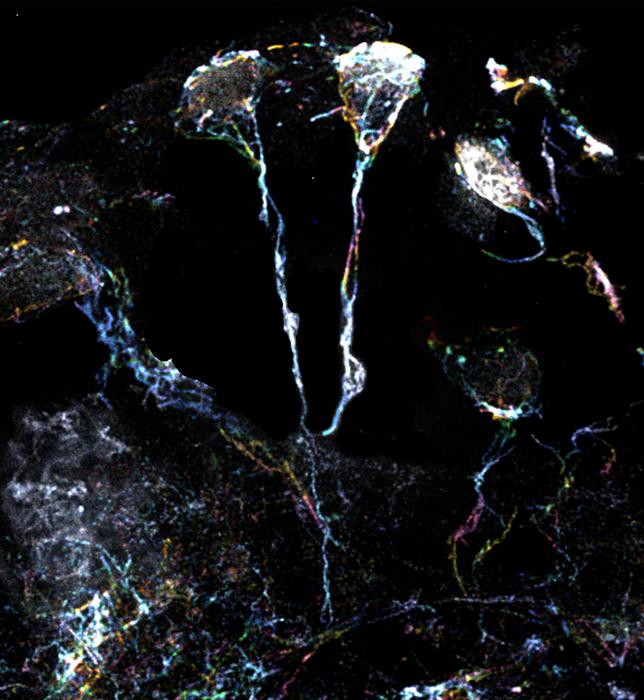

Using super-resolution microscopy with 10-times magnifying power, the team of scientists examined the tiny fibre structures that are a hallmark of dormant neural stem cells of fruit flies. These fine structures, around 1.5 µm in diameter (or 20 times smaller than the diameter of a human hair), are protrusions extending from the cell body, and are rich in actin or protein filaments. A specific type of Formin protein can activate these filaments and cause them to assemble.